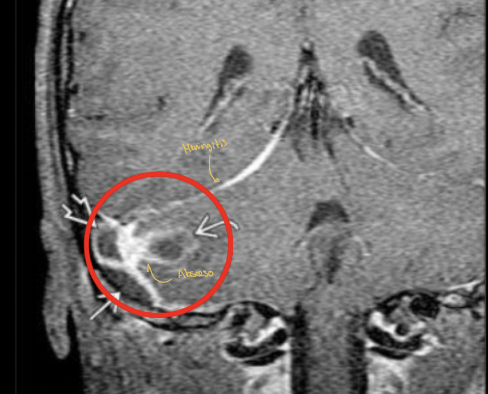

Q

Mastoiditis con invasión a SNC con un absceso que provoca una meningitis